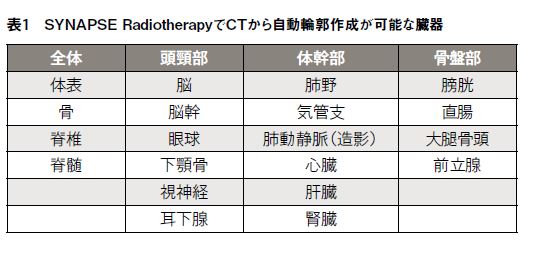

頭頸部、骨盤部領域および体幹部領域について、自動輪郭作成を行なった例を図1~3に示す。また、自動輪郭作成機能を用いて描出した輪郭と、医者により描出された輪郭との一致度(DICE 係数)を表2~4に示す。体幹部領域において、臨床に使用した治療計画に医師による輪郭描出がない場合、もしくは自動輪郭作成が正常に動作しなかった場合(心臓、肝臓で2例ずつ見られた)は評価から除外している。脊髄、直腸、心臓については上縁もしくは下縁の設定に差異があり、視神経は体積が非常に小さくスライス厚などの影響を受けやすいためDICE係数はやや小さい値を示しているものの、その他のリスク臓器については平均値および中央値でおよそ0.8~0.9となっており、高い一致度を示していることがわかる。また直腸に関してはガスが溜まっている場合は自動輪郭の精度はやや悪化するようである。肝臓については体積が大きく輪郭描出にも時間を要するが、自動で輪郭作成ができるような治療計画装置は少ない印象がある。SYNAPSE Radiotherapyは肝臓も良い精度で自動輪郭作成が可能である点は非常に評価が高いと感じる。